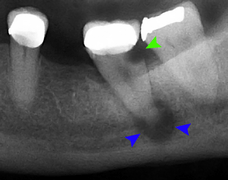

Decay (green) with apical abscess (blue)

The periodontal ligament becomes inflamed and there may be pain when biting or tapping on the tooth. On an X-ray, bone resporption appears as a radiolucent area around the end of the root, although this does not manifest immediately.[9]:228 Acute apical periodontitis is characterized by well-localized, spontaneous, persistent, moderate to severe pain.[4]:125–135 The alveolar process may be tender to palpation over the roots. The tooth may be raised in the socket and feel more prominent than the adjacent teeth.[4]:125–135